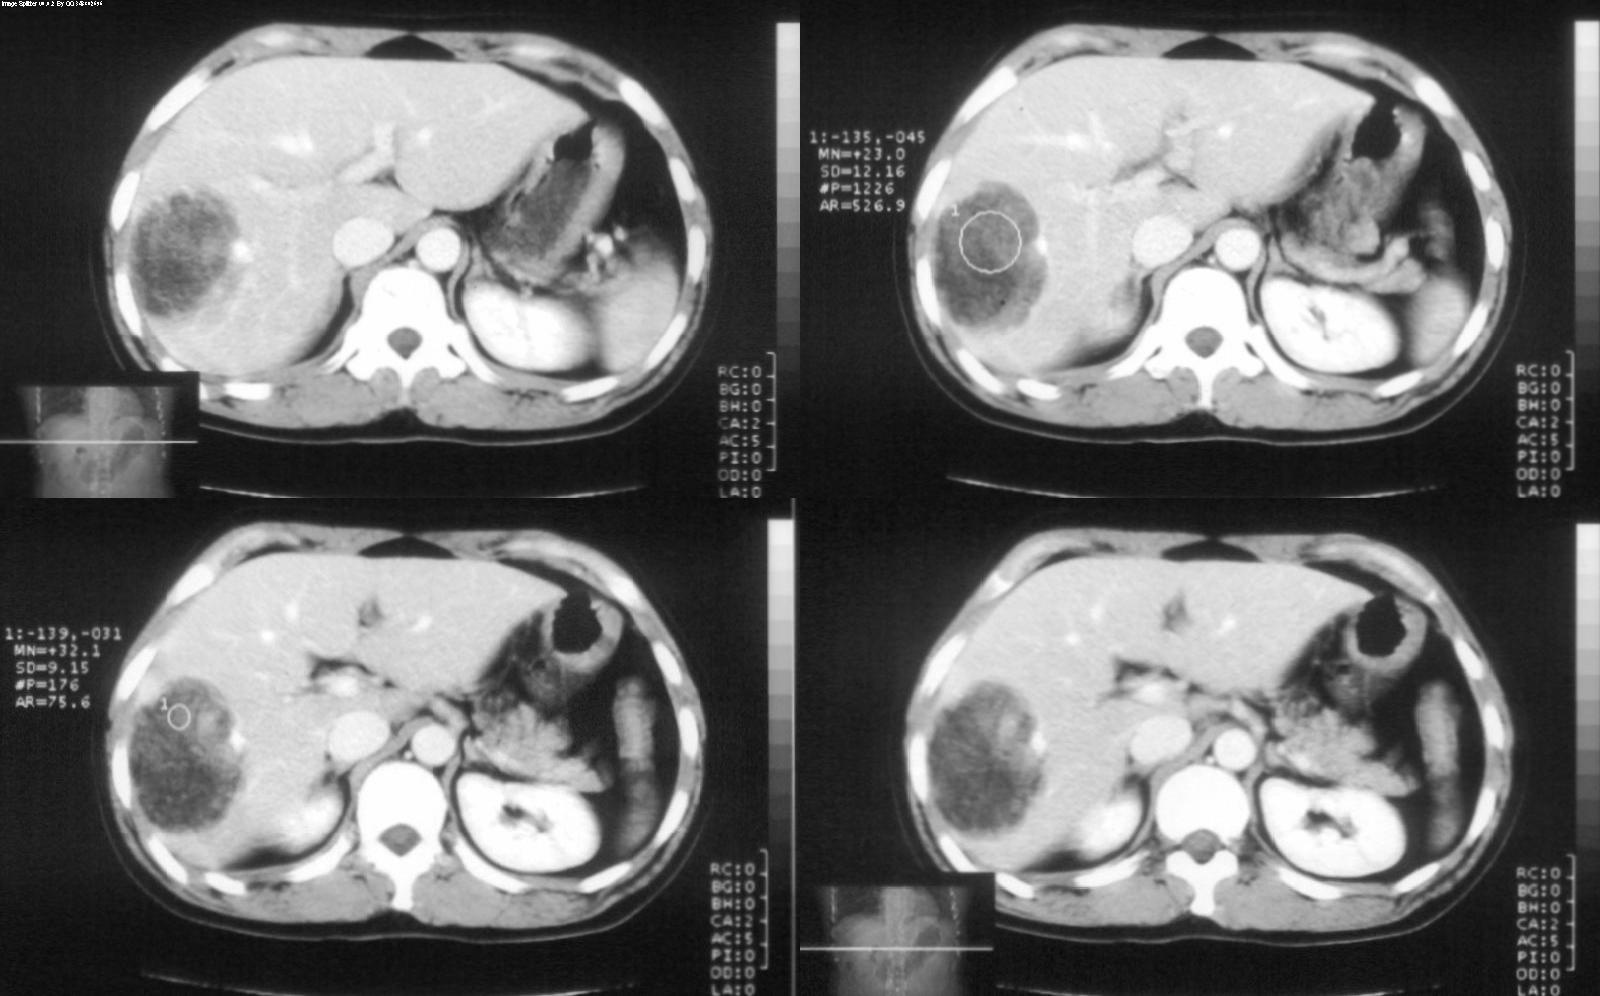

标题: CT28180:女性,42岁。体检时发占位。 [打印本页]

标题: CT28180:女性,42岁。体检时发占位。

ct值?肝脏血管平滑肌脂肪瘤

肝脏血管平滑肌脂肪瘤,边界结节样血管影持续性强化。

病灶多种成分,以脂肪为主,可见强化的血管肌肉成分,边界较清晰,综合考虑血管平滑肌脂肪瘤可能性大